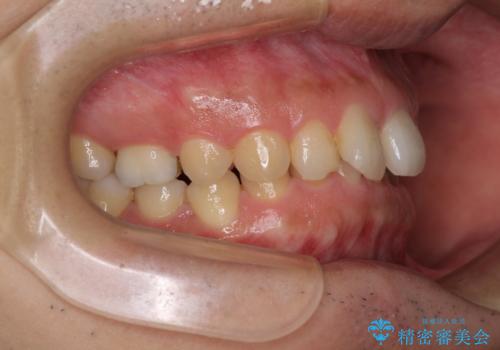

- 前歯の隙間を気にして来院された患者様です。

下顎前歯が見えなくなるくらいに深い咬み合わせであり、さらに上顎の正中が開くほど下の前歯が突き上げている状態でした。

奥歯は手前に倒れてしまっているため、後方に起き上がらせることで深い咬み合わせ・ディープバイトを改善する必要があります。